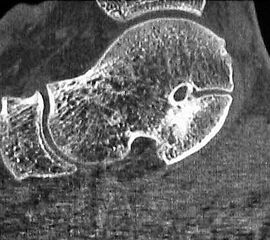

Z.n. Distorsion des Fußes mit „Ruptur“ der (vorbestehenden) talocalcanearen Coalitio. Die Wassereinlagerung in den an die Coalitio angrenzenden knöchernen Bezirken ist im MRT gut zu erkennen. Nach monatelangen Beschwerden spontane Besserung.

Abbildung 1

• Anhaltende Schmerzen nach vermeintlichen oder tatsächlichen Distorsionen („Aktivierung“ der Coalitio, vgl. Abb. 1)